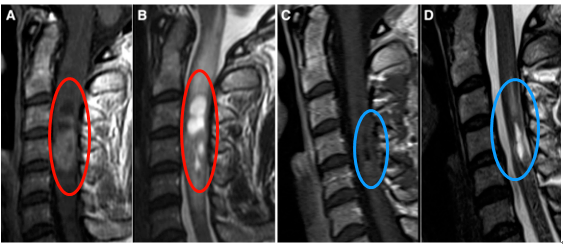

颈椎疼痛是现代很多职场人的通病,35岁的E女士长期伏案工作,脖子疼痛难忍,一直当成颈椎病治疗,近1个月疼痛使其难以入睡。同时出现上肢麻木、无力情况。一检查竟然是“脊髓室管膜瘤”(图A)在作祟。不仅如此,延髓也出现广泛水肿(图B)。

E女士辗转找到INC国际神经外科联合会(WFNS)立体定向与功能神经外科委员会主席德国Joachim K.Krauss教授,教授决定为其手术。在常规监测体感诱发电位监测下,采取后方入路(Posterior approaches),确定无任何神经损伤的情况下全切肿瘤。手术成功,术后12天复查,肿瘤全部切除(图C)。且术后水肿几乎完全消失,术前的颈椎疼痛也慢慢消失。术后两周出院,术后一个月回归正常工作与生活。

图:(A)术前T1 MR显示颈3-5占位。(B)T2 MRI显示延髓广泛水肿。(C)术后12天T1 MRI显示,肿瘤全部切除。(D)术后T2 MRI显示水肿几乎完全消失。